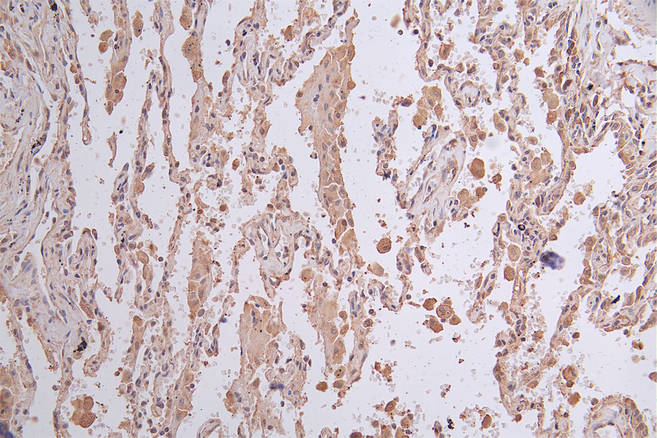

IHC image of CSB-RA156336A0HU diluted at 1:50 and staining in paraffin-embedded human lung cancer performed on a Leica BondTM system. After dewaxing and hydration, antigen retrieval was mediated by high pressure in a citrate buffer (pH 6.0). Section was blocked with 10% normal goat serum 30min at RT. Then primary antibody (1% BSA) was incubated at 4°C overnight. The primary is detected by a Goat anti-rabbit polymer IgG labeled by HRP and visualized using 0.26% DAB.

產品描述:CSB-RA156336A0HU LGR6重組單克隆抗體是經過嚴格驗證的高特異性科研工具,靶向LGR6(Leucine-rich repeat-containing G-protein coupled receptor 6),該蛋白屬于G蛋白偶聯受體家族成員,在干細胞調控及組織再生中發揮重要作用,尤其與表皮干細胞分化、毛囊發育及腫瘤發生相關。本抗體通過ELISA實驗驗證可特異性識別天然及重組LGR6蛋白,免疫組化(IHC)實驗顯示其在石蠟包埋組織中能清晰定位細胞膜表達,免疫熒光(IF)染色呈現高分辨率的亞細胞定位信號,流式細胞術(FC)進一步證實其適用于活細胞表面抗原檢測。推薦工作濃度為IHC/IF/FC 1:50-1:200,可滿足多樣本類型的實驗需求。該產品適用于干細胞生物學、組織再生機制研究、腫瘤微環境分析及發育生物學等領域,尤其為探索LGR6在表皮穩態維持、癌癥干細胞標志物篩選等方向提供可靠檢測工具。本產品僅供科學研究使用,需根據實驗體系優化具體條件。